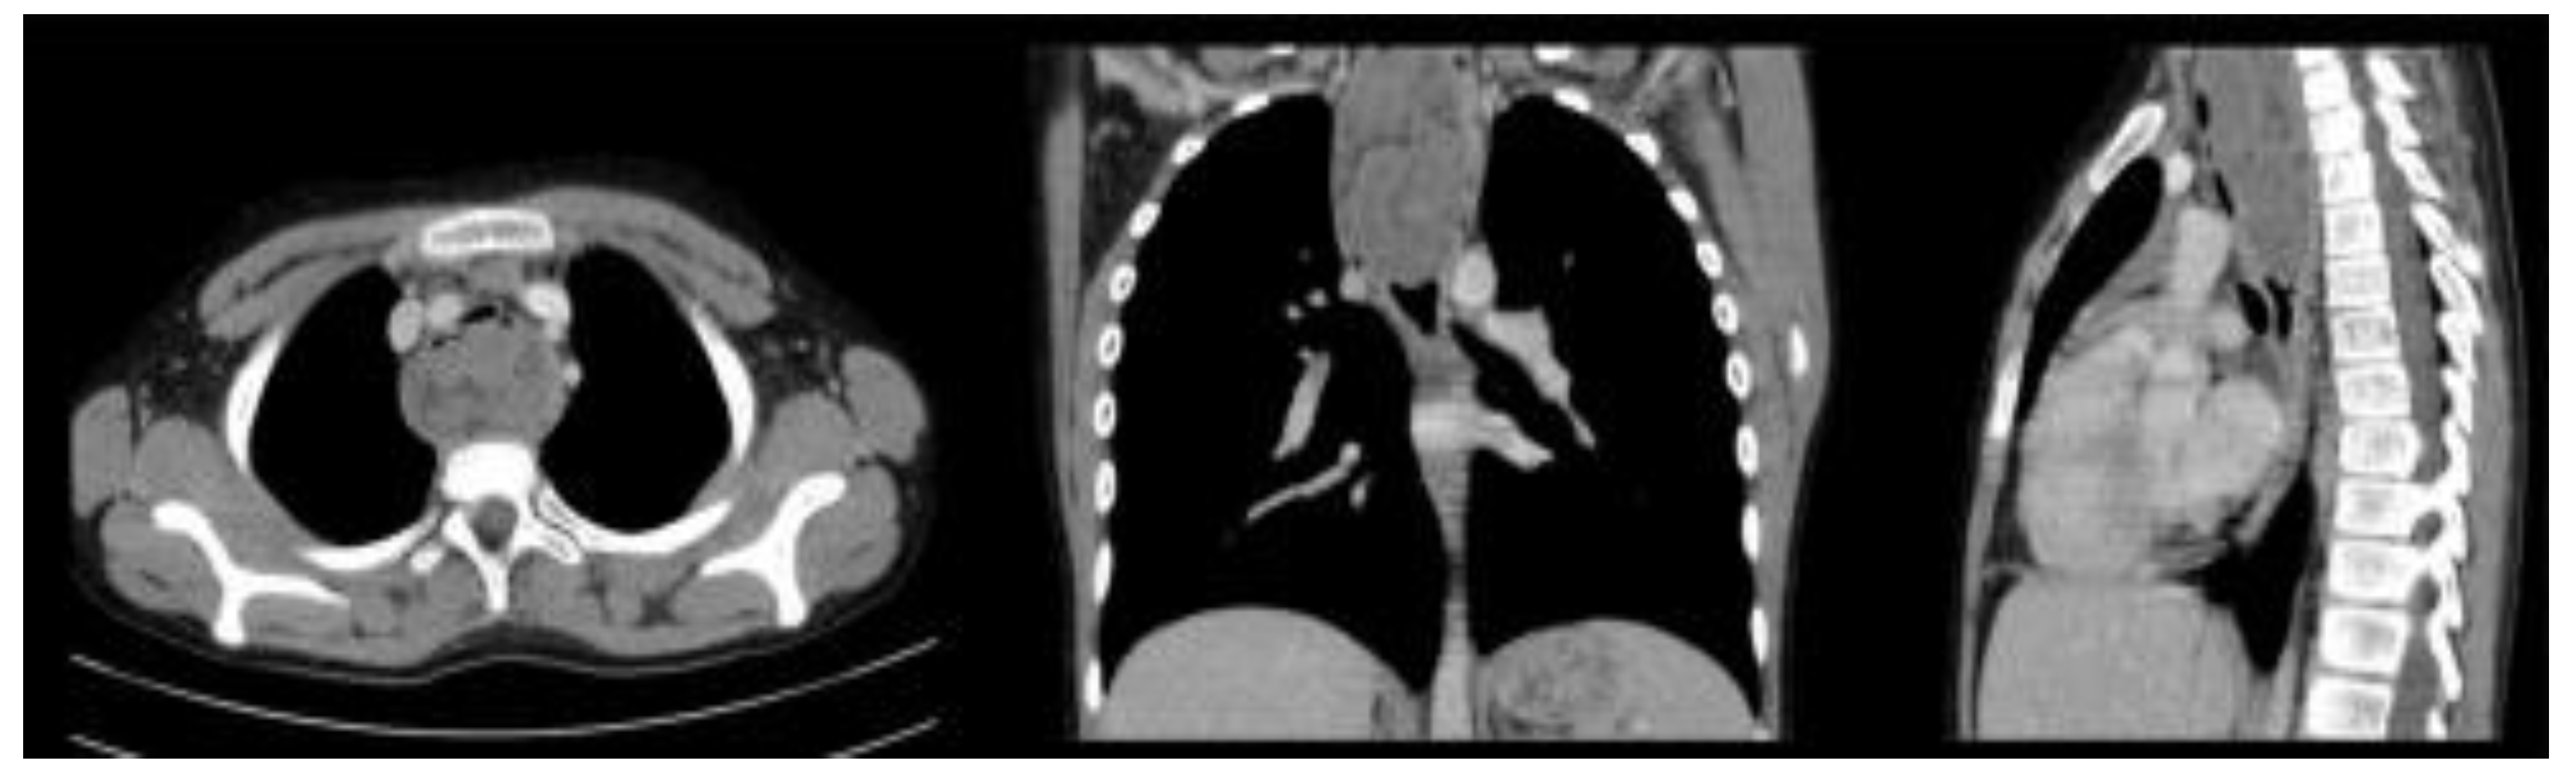

Case Report